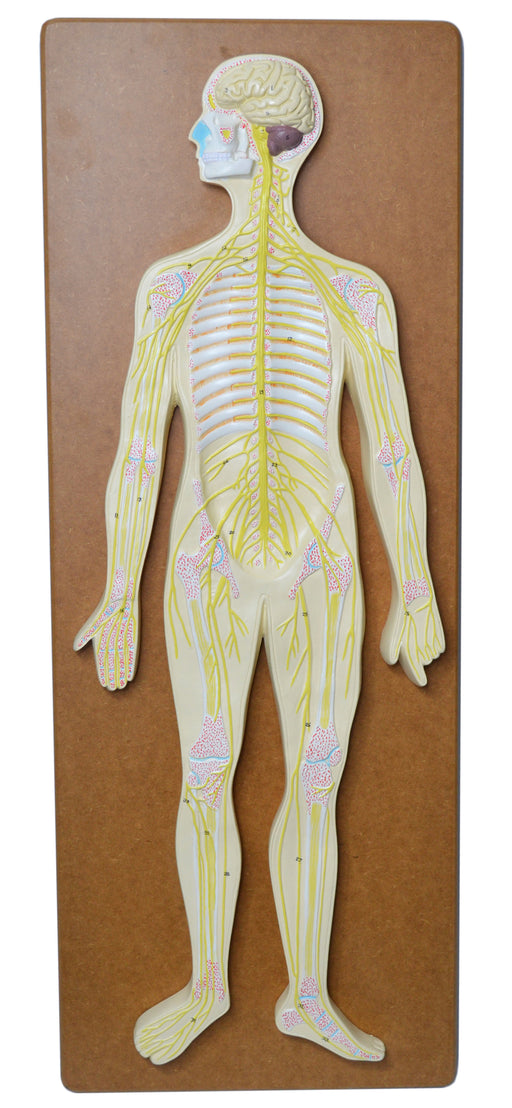

Nervous System Model, 32 Inch - Mounted - Includes Keycard - Great for Studying Structure - Eisco Labs

LIFELIKE DESIGN || 3-dimensional nervous system teaching demonstration model with lifelike design built from a custom mold DURABLE || Made of poly...

View full detailsAM16051 -